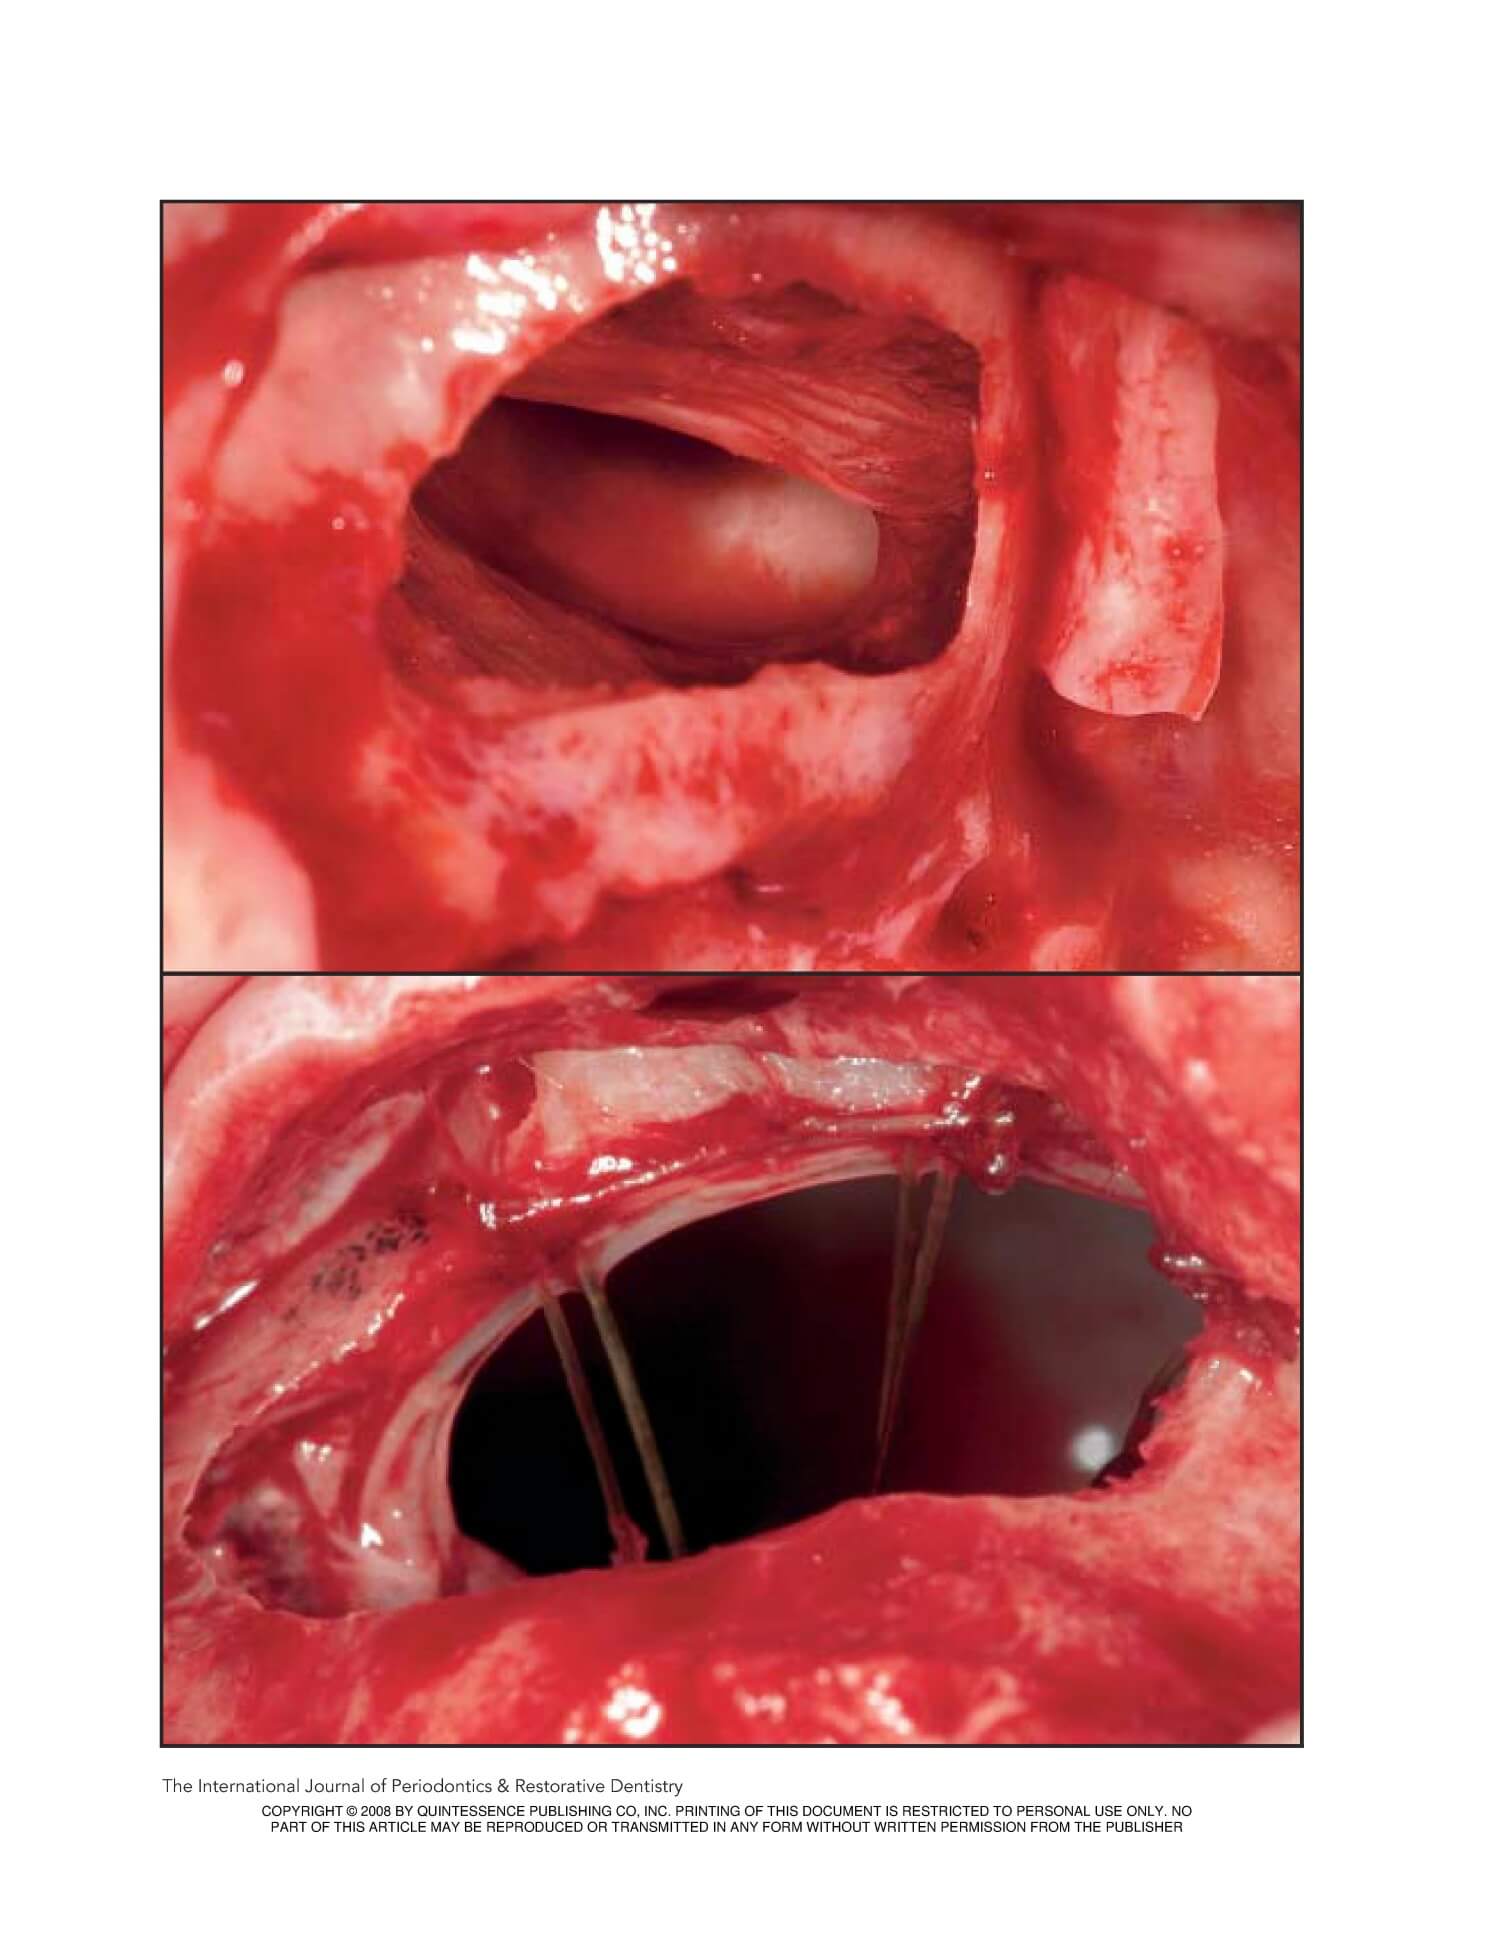

Repair of Large Sinus Membrane Perforations Using Stabilized Collagen Barrier Membranes: Surgical Techniques with Histologic and Radiographic Evidence of Success

Repair of Large Sinus Membrane Perforations Using Stabilized Collagen

Barrier Membranes: Surgical Techniqueswith Histologic and Radiographic

Evidence of Success